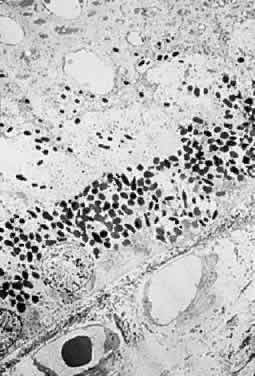

Clinicopathologic correlations of photic retinopathy have been reported by several investigators.16,75,76,144–146 Aware of prior studies by others on rats,25,147–150, Tso and coauthors reported the first of their series, performed on monkeys in 1972.75 They believed that the difference in their observations versus those published on rats might be related to the species of animal studied. Tso and coworkers created a model of chronic photic maculopathy through exposure to an indirect ophthalmoscope and found that significant changes were produced the first week after exposure, but a distinct maculopathy became evident only after an extended follow-up (5 months). They also described three stages in which this maculopathy occurs: initial degeneration in the first week, macrophagic response between the first week and first month, and repair and regeneration between the first and fifth month. Tso and associates also noted that, in the reparative phase, scarlike lesions noted clinically corresponded to proliferation of the RPE on a cellular level and, despite changes in the RPE, the overlying photoreceptors had regenerated. These clinicopathologic correlations led to more studies of macular response to light-induced injury. Histopathologic study of photic retinopathy in the human eye caused by exposure to light from the operating room microscope was reported by Green and Robertson in 1991.144 They describe the light and electron microscope findings of operating room microscope-induced maculopathy in a patient's eye after exposure to the light source for 60 minutes, 72 hours before enucleation for an iris melanoma (Figs 5 through 8). Findings in this acute form of photic retinopathy occurred mainly at the level of the RPE and photoreceptor layer and included the following: localized necrosis of the RPE; loss of the apical villi, plasma membranes, and cytoplasmic organelles of the RPE cells; extrusion of the retinal pigment epithelial pigment granules; and extensive disruption of the outer lamellae of the photoreceptors. Swollen mitochondria were present within the photoreceptor inner segments. Although this study was designed to address the issue of acute light-induced retinal damage, the additional finding of thinned retinal pigment epithelial cells, which apparently had migrated under injured RPE cells, suggests that a reparative process had already begun. The findings of Green and Robertson are consistent with those of Jaffe and coworkers reported in primates.146

Fig. 5. Light-microscopic appearance of an area of junction between phototoxic lesion (to the right) and normal unaffected retina and retinal pigment epithelium (to the left). In the lesion, the retina is edematous. An amorphous material is observed in the area of disrupted outer segements of the photoreceptors and the subretinal space. (Green WR, Robertson DM: Pathologic findings of photic retinopathy in the human eye. Am J Ophthalmol 112:520, 1991)

Fig. 6. Light-microscopic appearance of photic retinopathy with edematous outer retina and the edematous irregularly thickened retinal pigment epithelium. Most of the swelling involves the photoreceptor layer where an amorphous material largely replaces the outer segments. The photoreceptor nuclei appear relatively intact. (Green WR, Robertson DM: Pathologic findings of photic retinopathy in the human eye. Am J Ophthalmol 112:520, 1991)

Fig. 7. Electron-microscopic view of photic retinopathy with extensive derangement of the outer segments of the photoreceptors with distention (main figure), distortion, compaction, partial disintegration of the lamellar disks and disruption of plasma membranes. The inner segments of the cones are moderately swollen and the mitochondria are markedly distended. Inset shows details of the swollen mitochondria. (Green WR, Robertson DM: Pathologic findings of photic retinopathy in the human eye. Am J Ophthalmol 112:520, 1991)

Fig. 8. Electron-microscopic view of photic retinopathy. The retinal pigment epithelial cells are severely damaged with loss of plasma membranes, apical villous processes, basal infoldings and extrusion of pigment granules. Overlying the retinal pigment epithelial cells, a variably dense granular material containing fragments of outer segments is observed. (Green WR, Robertson DM: Pathologic findings of photic retinopathy in the human eye. Am J Ophthalmol 112:520, 1991)